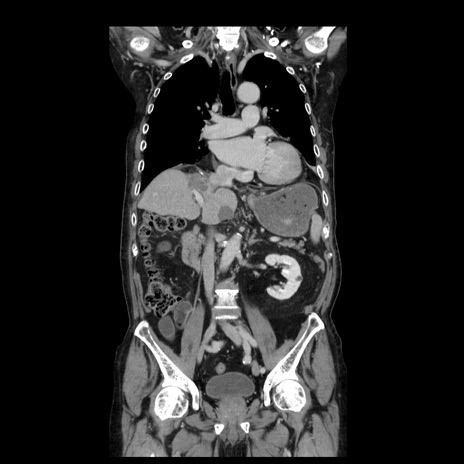

症例21(冠状断像)

横断像

【症例】70歳代男性

【主訴】腹痛

【現病歴】肝硬変・肝細胞癌にてかかりつけの方。約9時間前に食後より腹痛出現。症状が徐々に増悪し、嘔吐出現したため来院。

【既往歴】肝硬変、肝細胞癌(RFA、TACE後)

【身体所見】意識清明、表情苦悶様、BT 36℃、BP 129/78mmHg、P 88bpm、SpO2 97%(RA)、右上腹部から心窩部にかけて圧痛あり、反跳痛なし、筋性防御あり。

【データ】WBC 5800、CRP 0.16